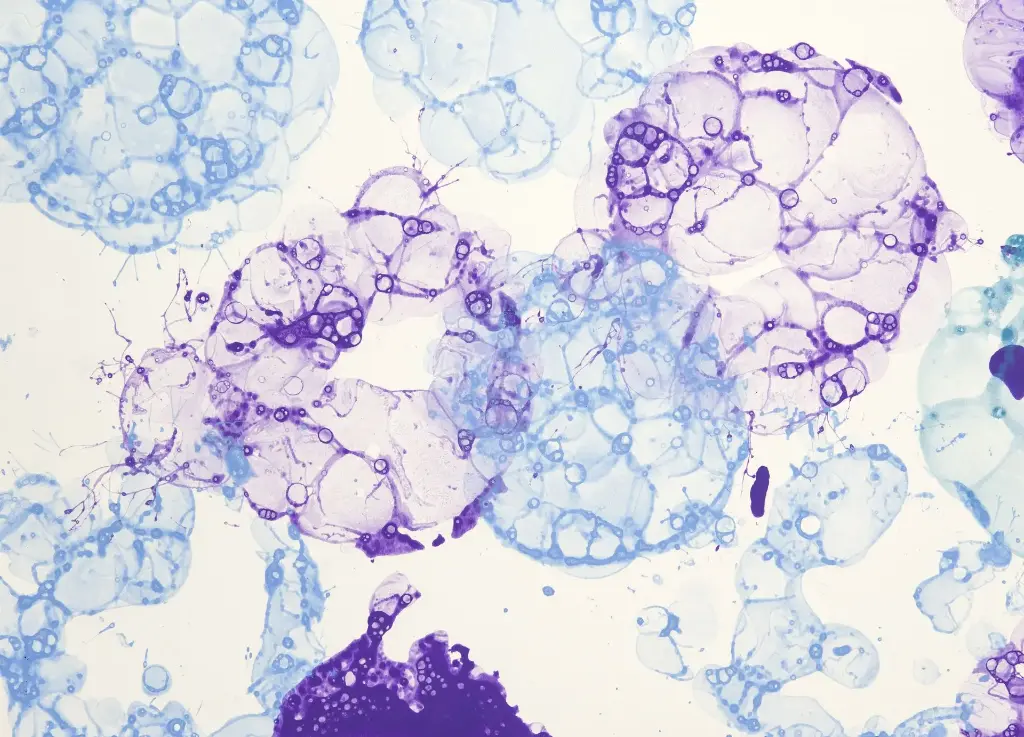

Structural Characteristics of Macrophages

Structur of Macrophages

Phagocytosis Process